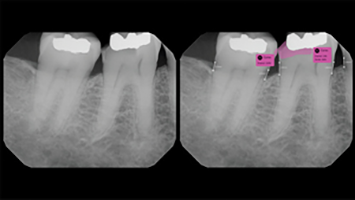

Carestream Dental and Overjet Partner to Give Doctors Greater Access to AI

Carestream Dental announced today it’s partnering with Overjet, the industry leader in dental artificial intelligence. The partnership gives Carestream Dental’s customers easy access to Overjet’s FDA-cleared, AI-powered X-ray analysis tool that detects decay, quantifies bone loss and highlights other areas of concern. Overjet also analyzes 18 months radiographs from previous visits and cross-references them with … Read more